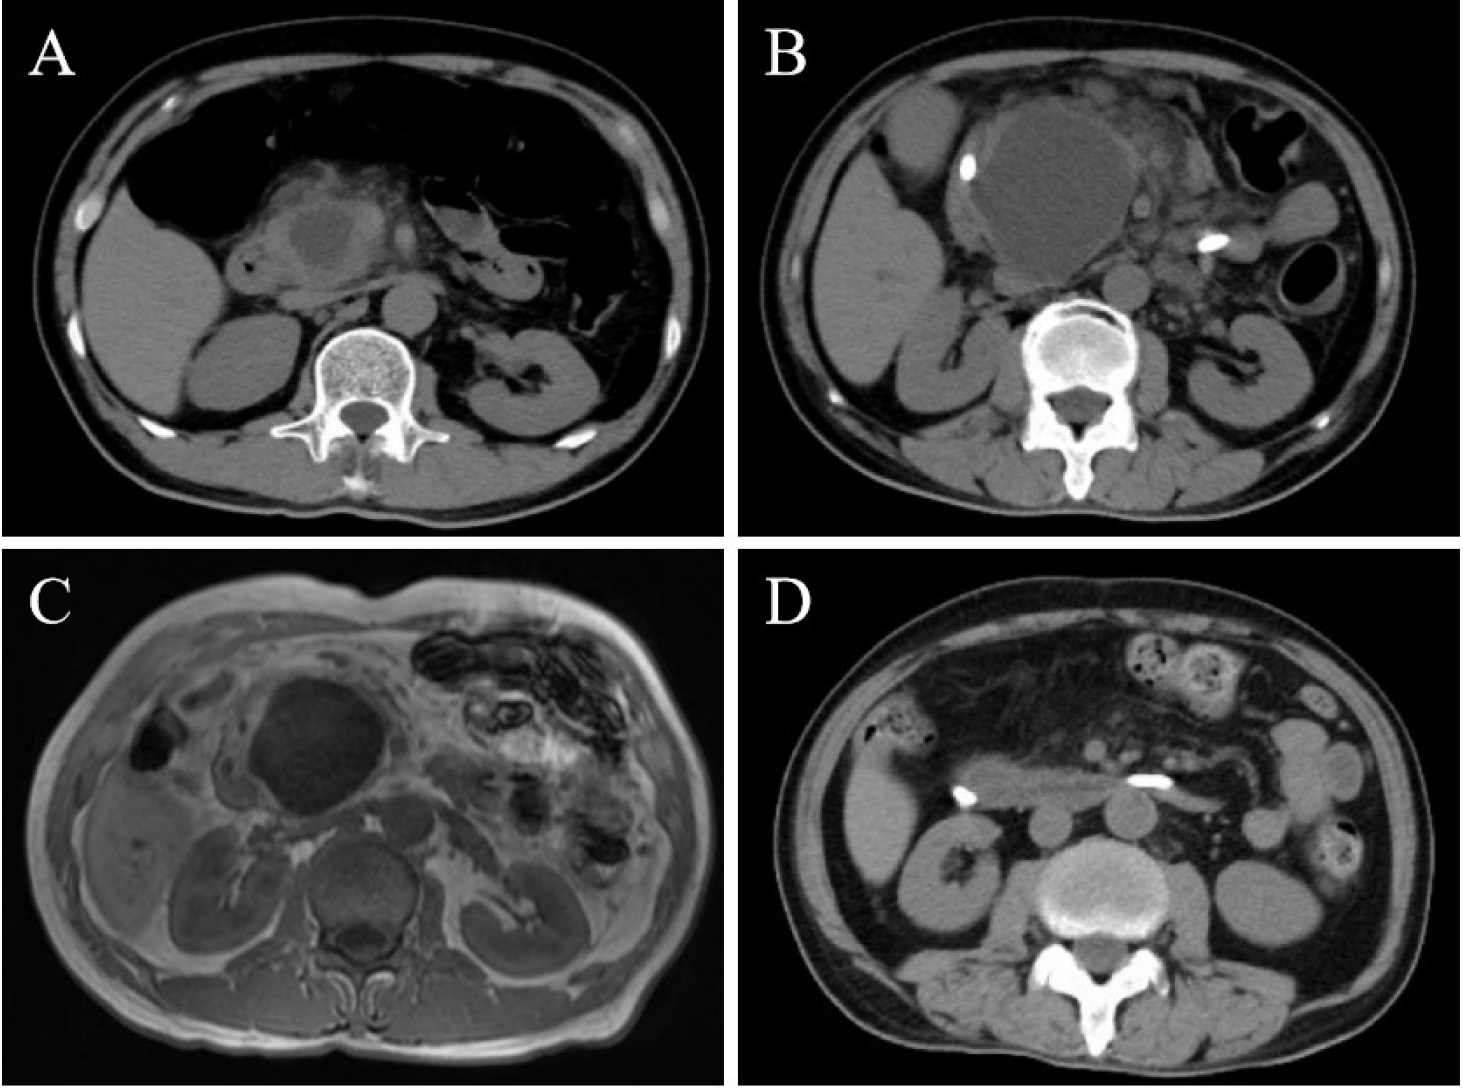

A 58-year-old male presented with an 8-day history of severe upper abdominal pain and vomiting. His medical history was unremarkable, with a normal abdominal computed tomography (CT) six months prior. Laboratory tests revealed elevated serum amylase, lipase, C-reactive protein, and D-dimer levels. CT scan identified a well-circumscribed 36 mm × 26 mm cystic lesion within the pancreatic head with peripancreatic exudation (Figure 1A). Despite supportive treatment for pancreatitis, symptoms persisted. Over two weeks, the lesion progressively enlarged to 67 mm × 49 mm on CT and magnetic resonance imaging (MRI), with branch pancreatic duct dilation (Figure 1B-C). Conventional etiologies such as biliary obstruction, hypertriglyceridemia, alcohol, drugs, or infection were excluded. An autoimmune workup revealed a normal immunoglobulin G4 (IgG4) level but positive antiphospholipid antibodies (aPL: Lupus anticoagulant (LA) 1.41 [positive: > 1.20]; anticardiolipin antibody (ACL)-IgM, 12.5 IgM phospholipid units (MPLU)/mL [positive: > 12.0]; beta-2 glycoprotein 1 (β2GP1)-IgM 60.1 AU/mL [positive: > 24.0]). The cystic lesion, inconsistent with intraductal papillary mucinous neoplasm (IPMN) or pseudocyst, led to the diagnosis of aPL-associated pancreatic cystic lesion with concurrent acute pancreatitis. Thromboembolic screening was negative. Methylprednisolone (40 mg/day) and low-molecular-weight heparin (4000 U/day) were administered, along with biliary and pancreatic duct stenting. As symptoms resolved, medications were tapered. Follow-up imaging demonstrated marked cyst regression (Figure 1D). Repeated testing after three months confirmed persistent aPL positivity (LA 1.28, ACL-IgM 14.9 MPLU/mL, β2GP1-IgM 42.6 AU/mL).

Images of the patient’s pancreas. Initial CT scan on admission (A) demonstrated a well-circumscribed cystic lesion (36 mm × 26 mm) within the pancreatic head, accompanied by peripancreatic exudation. CT scan after two weeks (B) showed progressive enlargement of the cyst to 67 mm × 49 mm, accompanied by dilation of the branch pancreatic ducts. Contrast-enhanced MRI (C) revealed hypointense on T1-weighted images and hyperintense on T2-weighted images within the pancreatic head, with no abnormal enhancement post-contrast administration. Follow-up CT scan after two weeks (D) demonstrated a significant reduction in cyst lesion size and resolution of peripancreatic exudation.